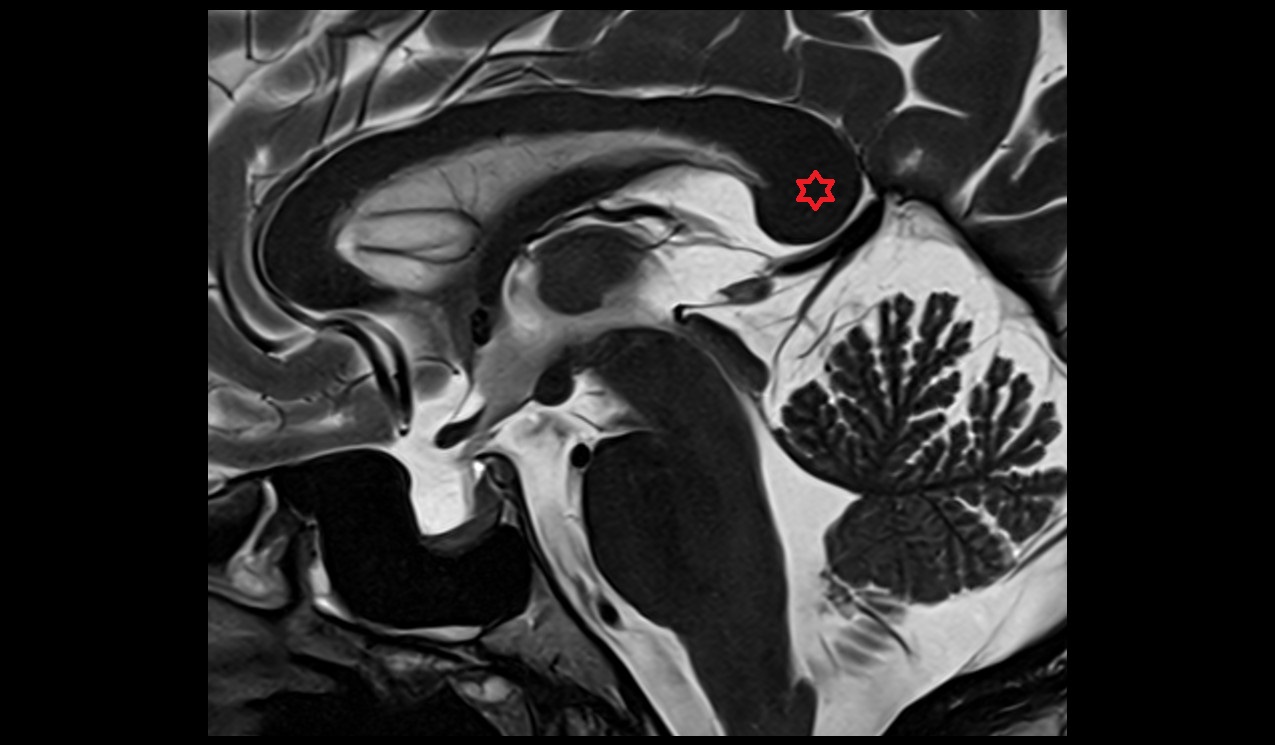

- Uterus

- Body of uterus

- Fundus of uterus

- Cervix of uterus

- Isthmus of uterus

- Vagina

- Fornix of the vagina

- Endometrium of uterus

- Myometrium of uterus

- Perimetrium of uterus

- Junctional zone of uterus